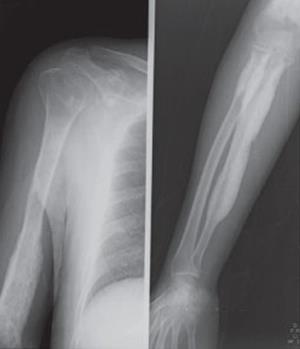

Врачи отмечают, что диагностика болезни Камурати-Энгельманна представляет собой сложный процесс, требующий комплексного подхода. Основные симптомы, такие как прогрессирующая деформация костей и мышечная слабость, могут быть легко спутаны с другими заболеваниями. Для точного диагноза специалисты рекомендуют проводить генетические тесты и рентгенографию, что позволяет выявить характерные изменения в костной ткани.

Диагностика болезни Камурати-Энгельманна включает клинический осмотр, анализ медицинской истории пациента и использование различных методов визуализации, таких как рентгенография и МРТ, для оценки состояния костей. Генетическое тестирование также может быть проведено для подтверждения диагноза, особенно если в семье уже есть случаи этого заболевания.